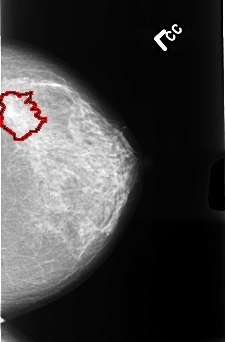

B_3477_1.LEFT_CC

FILE: B_3477_1.LEFT_CC.OVERLAY

TOTAL_ABNORMALITIES 1

ABNORMALITY 1

LESION_TYPE MASS SHAPE IRREGULAR-ARCHITECTURAL_DISTORTION MARGINS ILL_DEFINED-SPICULATED

ASSESSMENT 4

SUBTLETY 4

PATHOLOGY MALIGNANT

TOTAL_OUTLINES 1

BOUNDARY